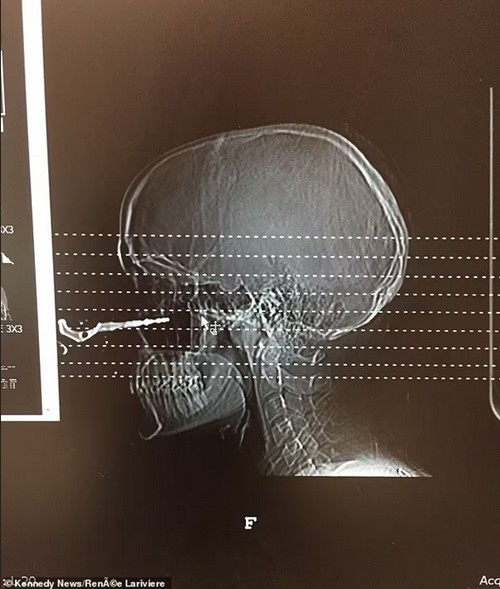

Người bạn lập tức gọi cấp cứu và Renée được đưa vào bệnh viện. Việc chụp X-quang cho thấy chiếc chìa khóa ghim sâu khoảng 2,5cm vào khoang mũi của Renée. Đến các bác sĩ và y tá cũng ngạc nhiên trước tai nạn này. Thậm chí, một bác sĩ trong phòng cấp cứu còn xin phép chụp một tấm ảnh của Renée để cho các sinh viên y khoa xem.

| Phim chụp cho thấy chìa khóa ghim vào khoang mũi của Renée. Ảnh: Renée Lariviere. |